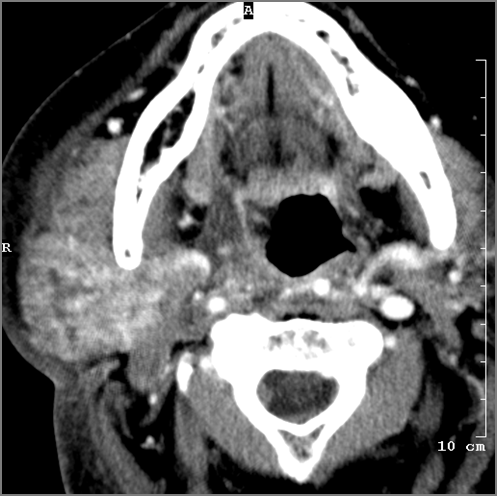

Nasopharynx Including Retropharyngeal Lymph Nodes

There is edema/abscess or likely suppurative retropharyngeal adenitis involving the nasopharynx or adjacent deep tissue spaces.

Oropharynx

There is edema/abscess tonsillar or otherwise or likely suppurative retropharyngeal adenitis involving the oropharynx or adjacent deep tissue spaces.